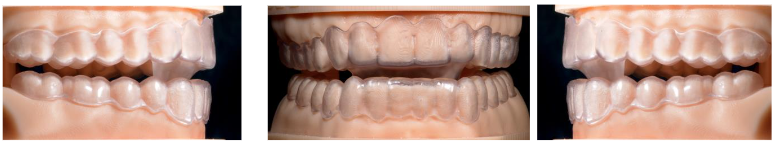

It is a double device, upper and lower, independent of each other, thermo-cured methacrylate cap type 0.75 mm thick, ESSIX, or made by stereolithography or 3D printing, which accurately covers the clinical crowns of all teeth. Generically called Sequential Transparent Aligners.

A Protrusion Ramp is incorporated or added to the upper element (maxillary arch) that we call Advancement Platform, which in a sagittal view resembles an “Elephant Trunk”.

The clinical procedure consists of taking records of the working models obtained by intraoral scanning of both dental arches, and of the palatal and lingual mucosa. The interocclusal record must be scanned, faithfully respecting the constructive bite in advance, with a flame-heated Godiva (jig). At 2/3 of the maximum clinical advancement.

The manufacturing is customized, to the exact measurement of each patient and each stage of treatment, by thermo-curing, stereolithography, or 3D printing. Regarding clinical management and given that physiologically a posterior and anterior disocclusion occurs between both arches, motivated by the condylar trajectory, following the articular eminences and, because it is closely related to the neuromuscular pattern of each patient (the more brachyfacial, the more posterior disocclusion), we must manage the vertical development of the posterior dentoalveolar processes and the anterior dentoalveolar dimension (incisal) depending on whether we need to intrude or extrude one or the other, at the same time that we will correct the transverse parameters correlating both arches.

Normally, when advancing the mandible, we will have to expand the upper arch or in severe cases we will have to do Maxillary Disjunction. By incorporating the AMAR™ Advancement Platform to clear aligners of any type, we can also perform all the individual dental movements that are necessary, incorporating as many attachments and auxiliary designs as we need to correct dental malocclusions, during the advancement phases, since there are no wings or occlusal ramps, in the posterolateral sectors, as there are with other elements (Precision Wings™, Twin-Block type ramps, Occlusal Ramps™, etc.)

All teeth have their clinical crowns and occlusal surfaces completely covered, so the upper and lower occlusal plane is completely controlled. If it were necessary to achieve greater anchorage of the appliances, we would design the trimming of the appliances, more towards the gingival, approaching the mucosal border of the maximum contour of the inserted, keratinized gum (Wala Ridge), avoiding the insertion of the buccal and lingual frenulums.